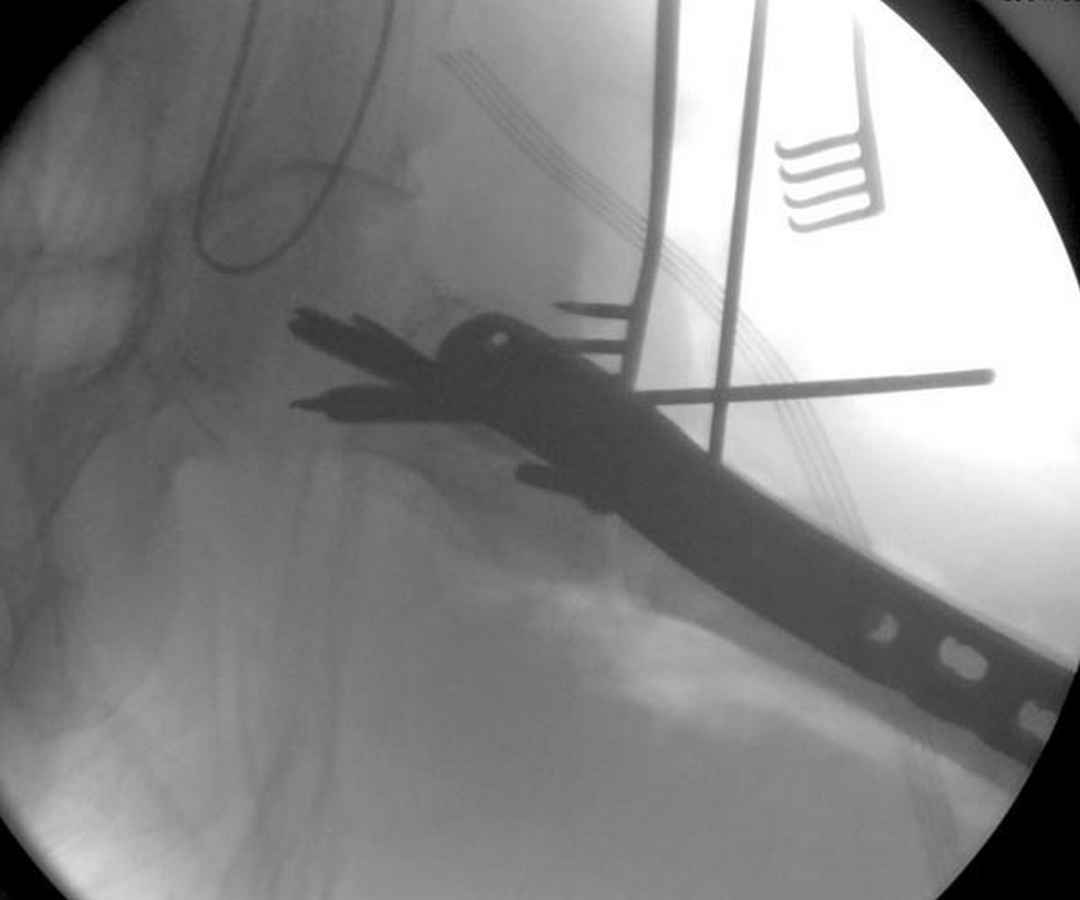

Здесь пара случаев фиксации похожих переломов:

первый высокоэнергетическая травма 36 лет